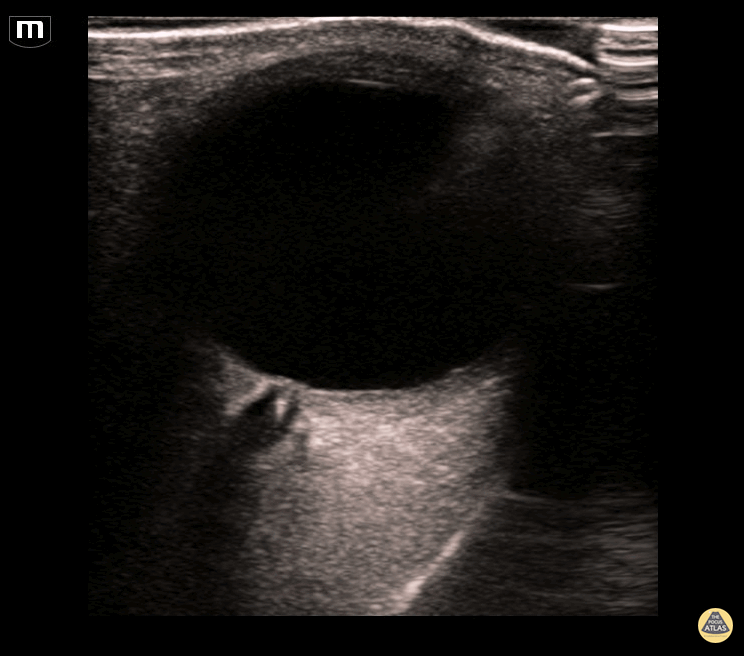

This point-of-care ocular ultrasound was obtained on an elderly female presenting with complete unilateral vision loss. This image demonstrates a "spot sign", which is a hyperechoic density seen at the distal aspect of the optic nerve, representing an embolus within the central retinal artery. Expedient diagnosis and treatment of central retinal artery occlusion has the potential to save vision to the affected eye. Anthony Capraro, Kevin Kucharski, Tyler Madison